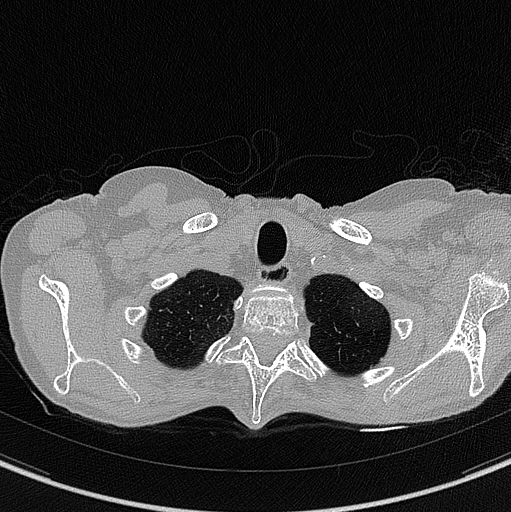

Example of CT Scan

The images below are examples of different acquisition for a sample subject that did a full exam.

exemple exemple

Inspiration acquisition without injection. Left mediastin reconstruction, rith parenchyme reconstruction.